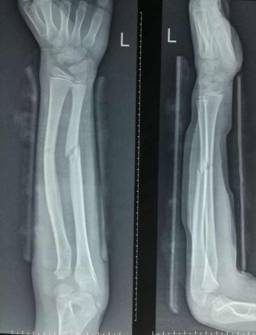

手法复位小夹板固定治疗骨折

西医手术先进全面:运用DCO理念,阶梯序贯抢救及治疗严重骨盆骨折、多发性、开放性重大骨折创伤;常规开展复杂骨盆髋臼骨折、手足显微外科的手术治疗;以最先进的生物学固定理念为指导,运用微创手术技术治疗骨折,包括:四肢长骨骨折的交锁髓内固定技术、MIPPO(微创经皮钢板内固定技术)、股骨近端骨折髓内固定技术(PFNA)、外固定支架固定技术等等均达国内先进水平。

中医骨伤特色明显:包括特色复位手法、传统夹板传承并革新;中药经验方药内服、外敷及离子导入疗法、中药水浴、熏蒸以及骨折后康复治疗等等可有效促进骨折愈合、治疗骨不连;吊兜悬吊牵引结合功能锻炼保守胸腰椎压缩性骨折;骨髓炎广泛开窗换药+外固定支架技术、感染骨段切除骨延长技术治疗,结合中医药辩证治疗等。

微创治疗肱骨干骨折

优点:闭合复位,不干扰骨折断端,中心固定,利于愈合。